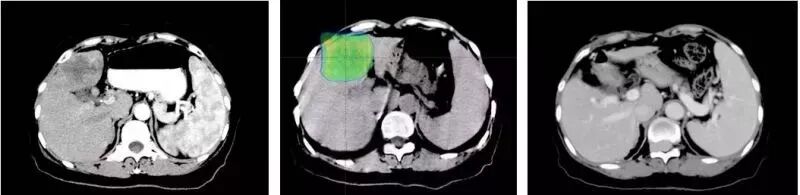

左:质子治疗前检查图像:肝右叶前段见类圆形低密度影,呈不均匀强化,边界清楚

中:质子治疗剂量分布:剂量分布均匀,包绕肿瘤组织,对周围正常肝组织保护好

右:质子治疗九年后复查图像:肝右叶肿瘤消失